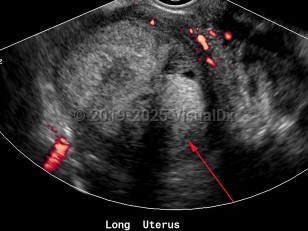

Endometrial carcinoma

Endometrial carcinomas are more common in women of European descent and more likely to develop after menopause.

Most commonly, endometrial carcinoma develops in conditions that expose the uterus to estrogen, either for very prolonged periods of time, without opposing progesterone, or both. As such, obesity, polycystic ovarian syndrome (PCOS), diabetes mellitus type 1 and type 2, anovulation, nulliparity, tamoxifen use (in postmenopausal woman), prolonged hormone replacement therapy with estrogen alone, and early menarche or late menopause are all variably potent risk factors for endometrial carcinoma.